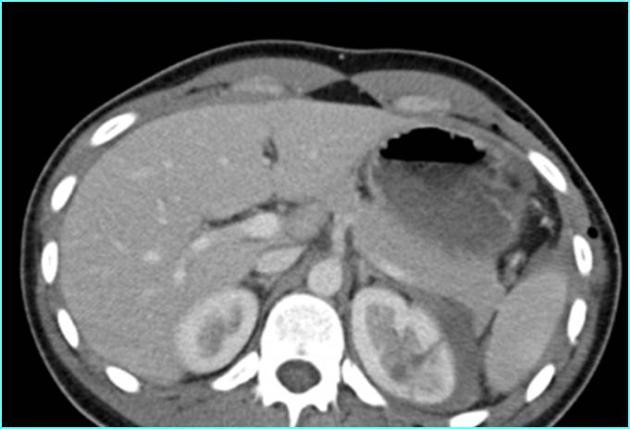

Incidentally seen liver lesion.

Isodense to liver on other phases

FNH

homogeneously hypervascular on arterial phase imaging and nearly isodense to liver on other phases; the additional presence of a central scar is essentially pathognomonic.

—> in a younger woman w/o hx of cancer, can be dx from the CT appearance

—>hemangioma would be hypervascular but isodense to vessels, not liver.